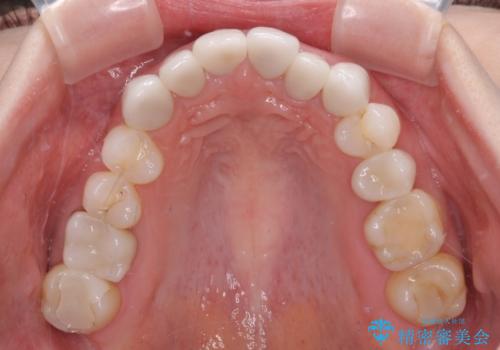

- 全体的なデコボコと、奥歯の欠損を放置した結果倒れ込んだ奥歯などを気にして来院された患者様です。

ワイヤー矯正の方が理想的な仕上がりとできる状態でしたが、上顎前歯にクラウンが装着されているため、インビザラインにて矯正治療を行うこととしました。

インビザラインのみで対応できないときにはワイヤー矯正を併用することとし、矯正治療後にはオールセラミッククラウンによる補綴治療を行うこととしました。

矯正治療自体はインビザラインで満足のいく仕上がりとなりました。

前歯は根管治療が必要となり、元々舌側に入り込んでいた左上2番目の歯は歯周外科処置により歯肉ラインを整えることとしました。

欠損部位は傾斜歯軸を起き上がらせることができたため、オールセラミッククブリッジにて補綴治療を行いました。

全顎的に満足のいく仕上がりとなりました。